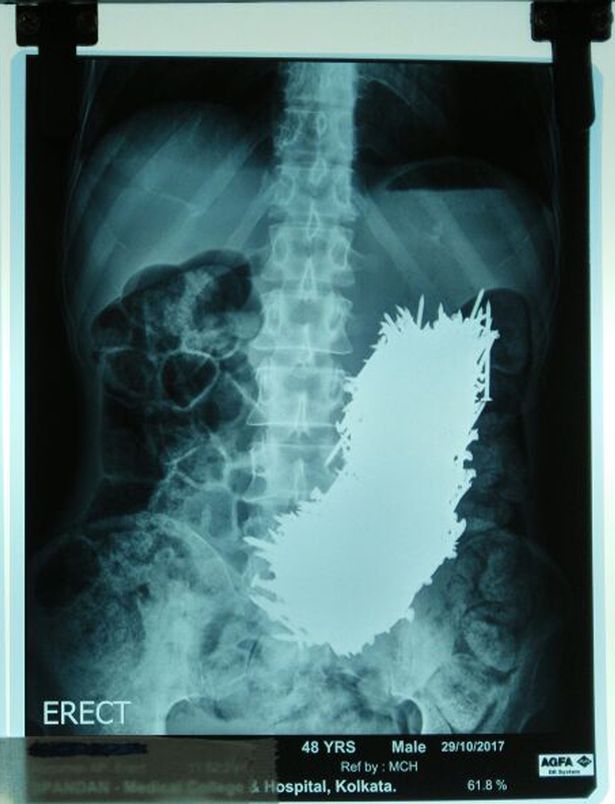

02/11/2017 16:15Dùng nam châm hút 600 đinh sắt ra khỏi bụng bệnh nhân

Pradip Kumar Dhali, 48 tuổi, được gia đình đưa đến bệnh viện sau khi ông bị đau bụng cấp tính. Sự việc xảy ra cách đây khoảng hai tháng nhưng mới được công bố gần đây, Mirror đưa tin.

Các bác sĩ đã sốc khi thấy ảnh chụp siêu âm với tổng cộng 600 đinh sắt trong bụng. Sau 2 ngày quan sát, họ quyết định dùng nam châm trong quá trình phẫu thuật, hút đinh sắt ra khỏi bụng bệnh nhân.

Rất may là không có chiếc đinh nào làm thủng dạ dày của ông.

Siddhartha Biswas, bác sĩ đứng đầu cuộc phẫu thuật, cho biết: "Tháng trước, gia đình bệnh nhân đưa cho chúng tôi xem ảnh siêu âm, tôi đã sốc khi thấy đinh trong bụng ông ấy.

"Chúng tôi quyết định phẫu thuật. Điều này rất nguy hiểm vì bụng của ông đã phình to lạ thường và chứa đầy đinh. Nhưng rất may không có cái đinh nào xuyên thủng dạ dày.

"Chúng tôi cắt một phần dạ dày của bệnh nhân và dùng nam châm để lấy đinh ra, từng cái một. Có hơn 600 đinh trong đó. Chúng tôi phải đảm bảo tất cả đinh ông nuốt phải được lấy ra."

Pradip, một bệnh nhân tâm thần phân liệt, có thói quen ăn vật thể lạ. Nhưng gia đình ông vẫn kinh ngạc khi phát hiện ông nuốt hàng trăm cái đinh.

Bác sĩ Biswas nói: "Gia đình được bác sĩ tâm thần của Pradip dặn là không nên làm phiền ông ấy. Vì thế họ không bận tâm nhiều đến việc ông ấy ăn gì. Họ cũng không hề biết ông ấy lấy đinh ở đâu".